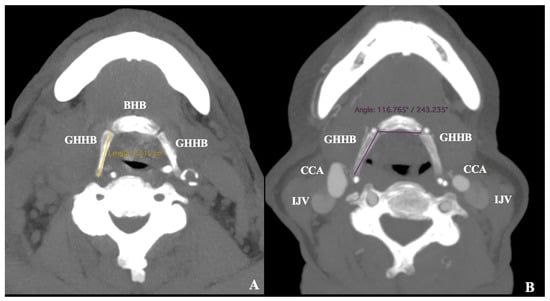

- In cases of suprahyoid CB, the minimum distance GH-CCA was measured (Figure 3)

- In cases of infrahyoid CB, the minimum distances GH-ICA and GH-ECA were measured (Figure 3)